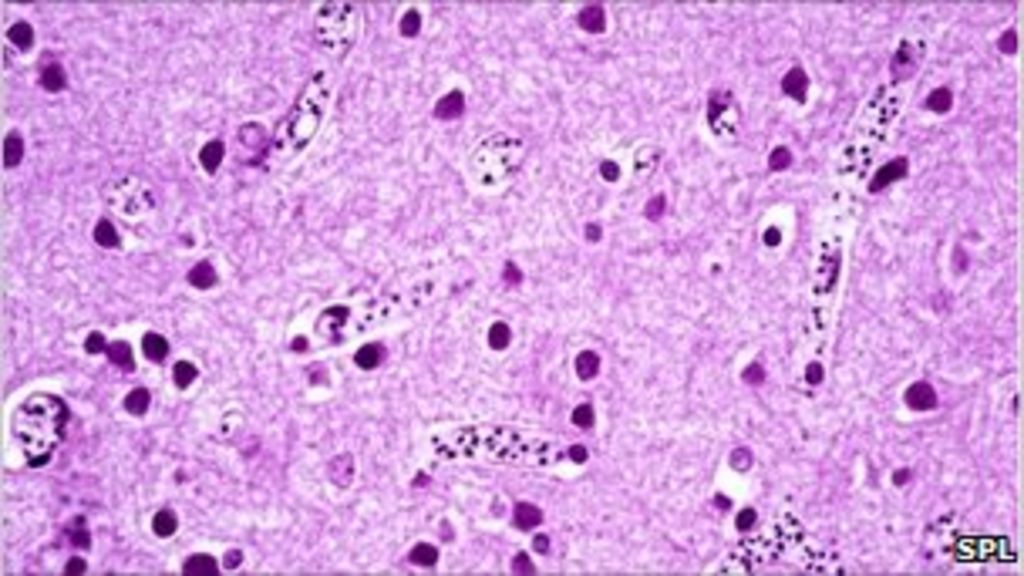

From pixnio.com

Free picture histopathology, malaria, pigment, brain, capillaries Medicine For Brain Malaria Researchers at the national institutes of health found evidence that specific immune cells may play a key role in the devastating effects of cerebral malaria, a severe form of malaria that mainly affects young. All patients with plasmodium falciparum malaria with neurologic. Ensure prompt diagnosis followed by immediate treatment. Treatment of severe and cerebral malaria. Cerebral malaria is a medical. Medicine For Brain Malaria.

Free picture histopathology, malaria, brain, plasmodium falciparum Medicine For Brain Malaria Treatment is much more effective when it’s started early. The right medication and correct dose can treat malaria. Treatment of severe and cerebral malaria. All patients with plasmodium falciparum malaria with neurologic. Treatment is with parenteral artemisinin derivatives and electrolyte correction, usually in the setting of an intensive care unit, as well as symptomatic treatment (e.g. It’s essential to seek. Medicine For Brain Malaria.